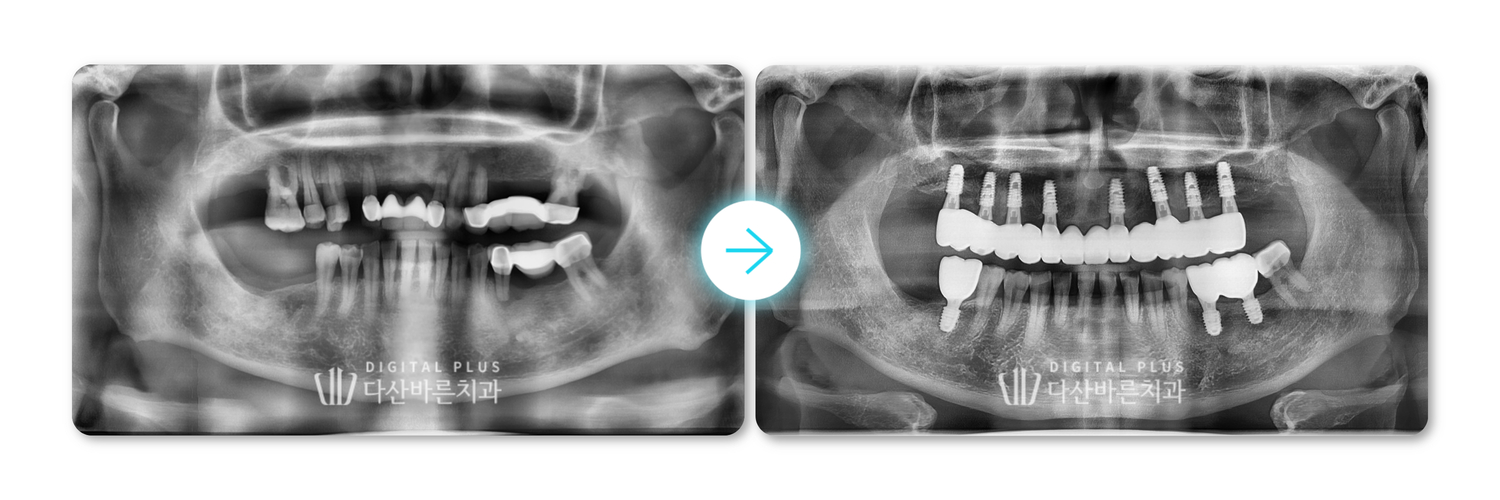

[환자 연령] 60대

[내원 사유] 위쪽 디지털 풀아치 상담 원해요

[치료 내용] 상악 디지털 전체임플란트